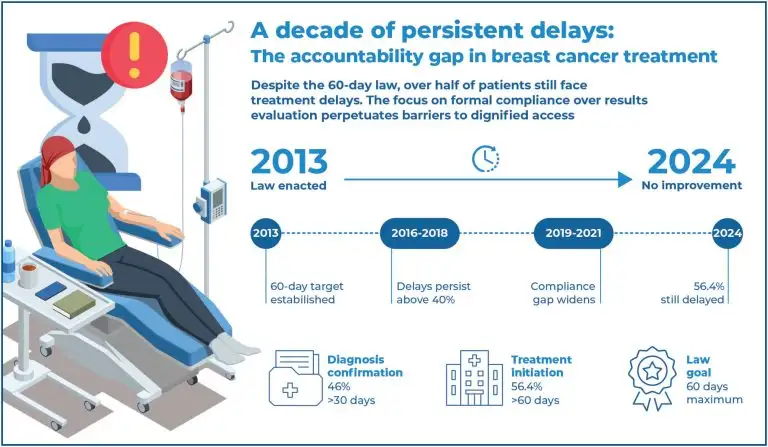

Highlights ■ Law 12.732/12 had limited impact on breast cancertreatment access. ■ Persistent delays in breast cancer diagnosis & treatment in São Paulo, 2013-2024. ■ External oversight prioritizes compliance, not direct results evaluation. ■ Reorient oversight to induce greater managerial accountability. ABSTRACT Objective: This article analyzed the impact of Law No. 12,732/2012 on breast cancer care in São Paulo State (Brazil) between 2013 and 2024, as well as the role of external oversight. Methods: This qualitative-quantitative study used 58,892 records […]